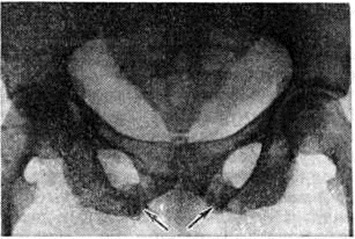

Рис. 3.

Рентгенограмма таза больной С хронической почечной недостаточностью: резкий остеопороз и образование очагов (указаны стрелками) патологической функциональной перестройки в костях таза.